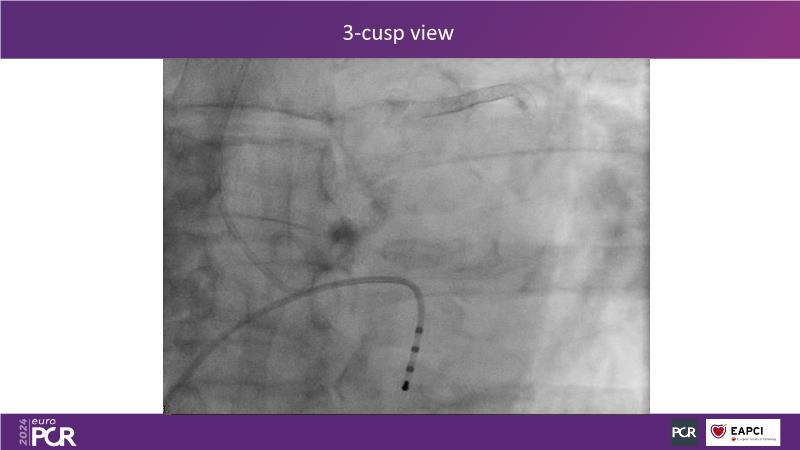

In this session, explore the next-generation balloon-expandable Myval Octacor THV, focusing on its key features, procedural impact, and potential clinical benefits. Understand the procedural steps for planning and implanting it, especially for intermediate and extra-large sizes, using the Octalign technique. Learn about the unmet clinical need of considering TAVI in extra-large annuli, and the clinical significance and relevance of Myval Octacor THV XL sizes. Gain insights from experts on best-in-class TAVI practices, including pre-procedural imaging, sizing rationale, treatment strategies, procedural tips and tricks, and post-procedural management. Additionally, review the latest outcomes from the LANDMARK pivotal RCT and other clinical evidence to date.

- To learn from the experts best-in-the-class TAVI practice: pre-procedural (imaging, sizing rationale, treatment strategy), procedural tips & tricks and post-procedural management